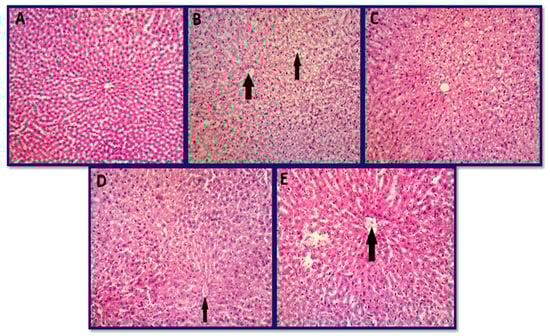

3.6.1. Histopathology of Liver